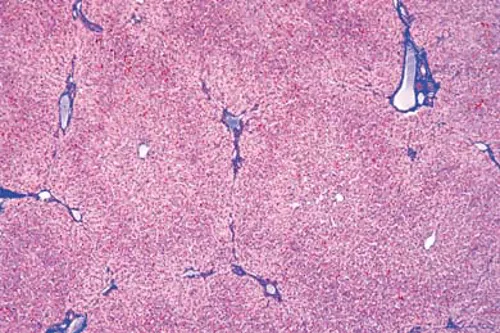

Microfoto van een doorsnede van een menselijke lever. De doorsnede is zo gelegd dat het mogelijk is om de individuele leverkwabben als hoekige 'eilanden' te zien, elk met zijn eigen centrale ader omgeven door de individuele levercellen - de zogenaamde hepatocyten. Het preparaat laat zien hoe de celdichtheid en de afwezigheid van bindweefsel de lever tot een zeer zacht en doorlatend orgaan maakt. De structuur van de leverlobben geeft een goed beeld van hoe de bloedfiltratie vanuit de centrale ader naar buiten toe verloopt.

Het preparaat kan worden gebruikt in lessen biologie en geneeskunde om de anatomie en fysiologie van de lever te illustreren. Het is ook een product dat een idee geeft van hoe de vele celtypen in het lichaam gespecialiseerd zijn voor hun eigen functie en dat dit vaak niet alleen te zien is aan de individuele cellen, maar ook aan hoe de cellen zich organiseren in het weefsel.